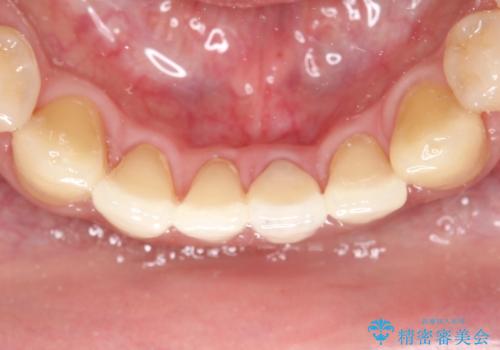

下顎前歯のセラミッククラウン

- 前歯の審美障害を主訴に来院されました。

根管治療を行なったのちオールセラミッククラウン(スタンダード)にて修復治療を行なっております。

歯髄壊死により変色した歯は根管治療が必要となります。